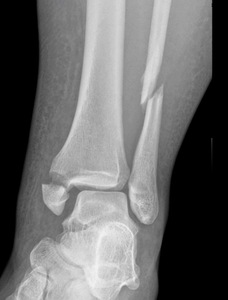

We don’t necessarily operate on all ankle fractures. The following x-ray demonstrates a stable ankle fracture (Figure 1).

This patient can start immediate, protected, weight bearing in a boot or air cast. If you’re not practicing that, you should! I still see elderly patients with a small “crack” like this, that are kept non-weight bearing for two months. Don’t do that! These are stable injuries. They can start immediate, protected, weight bearing in a boot, and can wean out of the boot as tolerated.